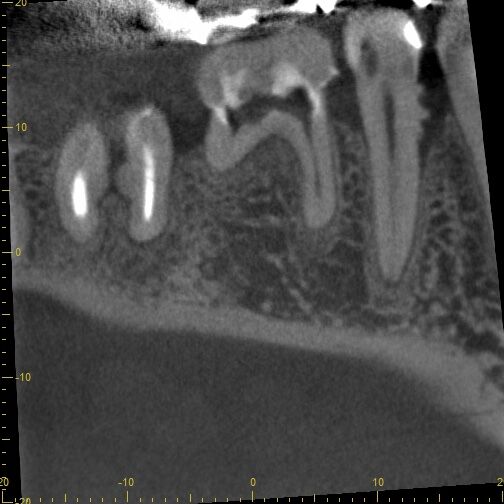

↑これはCT画像です。右下5番の近心,,,どうです

もう歯石の除去もCTで確認する時代ですよね〜デンタルは平面しかみえないし、360度根の周りの骨吸収は見えないし。デジタル化しているのに、歯科衛生士は未だ手探りの歯石の除去と見えない想像の世界での骨吸収との戦い。そして妄想で骨が治ったとか...ね。。。妄想しかないから、口腔衛生指導で綺麗になった口腔内写真しか症例で出せない。